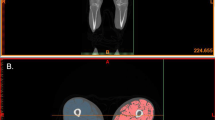

A weight-bearing anteroposterior radiograph of the entire lower extremities was obtained that included both legs; the radiograph was taken while the patient was in standing position with the knees extended, and there was a 2-m distance between knees and the X-ray bulb. The X-rays were acquired by a radiologist from Akita Hospital. The anatomical axis of the limb was measured from the radiograph as the femorotibial angle (FTA) between the femur anatomical axis and the tibia mechanical axis using Management Integrate Network Diagnosis Solution (MIND Solution; LEOCLAN Co., Ltd., Osaka, Japan) by the first author. The femur anatomical axis was measured from the distal half of the femur, and the tibia mechanical axis was defined as a line connecting the center of the knee and the ankle (Fig. 1) [16]. The measurement of FTA in the right side of randomly selected 20 patients was performed by the first author two times separately to evaluate intraobserver reproducibility. The Japanese Knee Osteoarthritis Measure (JKOM) score (100 full points) was used to evaluate knee pain (32 full points), ADLs (60 full points), and health perception (8 full points); higher JKOM scores were worse [17].

Weight-bearing anteroposterior radiograph of the entire lower extremities. Solid lines represent the femur anatomical axis in the distal one-half of the femur, and dotted lines represent the tibial mechanical axis between the center of the knee and the ankle. Lateral angles (femorotibial angle) are the anatomical axes of the limbs

Thigh circumference and myofascial CSA at the 10% distal region were semi-automatically segmented using MIPAV software (Fig. 1). Yoshiko et al. [19] reported that significant differences in the intra-MAT composition between healthy young individuals and elderly individuals were observed at the distal region of the thigh. Therefore, CSA at the 10% distal region was analyzed in the present study. SAT CSA (cm2) was calculated as thigh circumference CSA—myofascial CSA. Inter-MAT and intra-MAT areas (cm²) were measured by a radiologist from Akita Hospital using MIPAV software as follows [19, 20]: (1) The image heterogeneity at the distal 10% region was corrected using a nonparametric nonuniform intensity normalization (N3) algorithm. (2) In the corrected image, four regions of interest of 5 mm × 5 mm were set on muscle tissue and adipose tissue to define the Otsu threshold value using histogram shape-based thresholding techniques. Three times the mean values were used as the Otsu threshold value; (3) the pixel with higher value than Otsu threshold value was recognized as adipose tissue and the adipose tissue area was calculated. The inter-MAT area (cm2) was calculated as the adipose tissue within the myofascial CSA, excluding individual muscles, vessels, nerve tissue and bone area (Fig. 1, right upper quadrant). The intra-MAT area (cm2) was calculated within individual muscles (Fig. 1, right lower quadrant). To test the reproducibility of MAT measurement, inter and intra-MAT of the right thighs of randomly selected patients were analyzed twice by the radiologist, with a 2-month interval between the two measurement times.